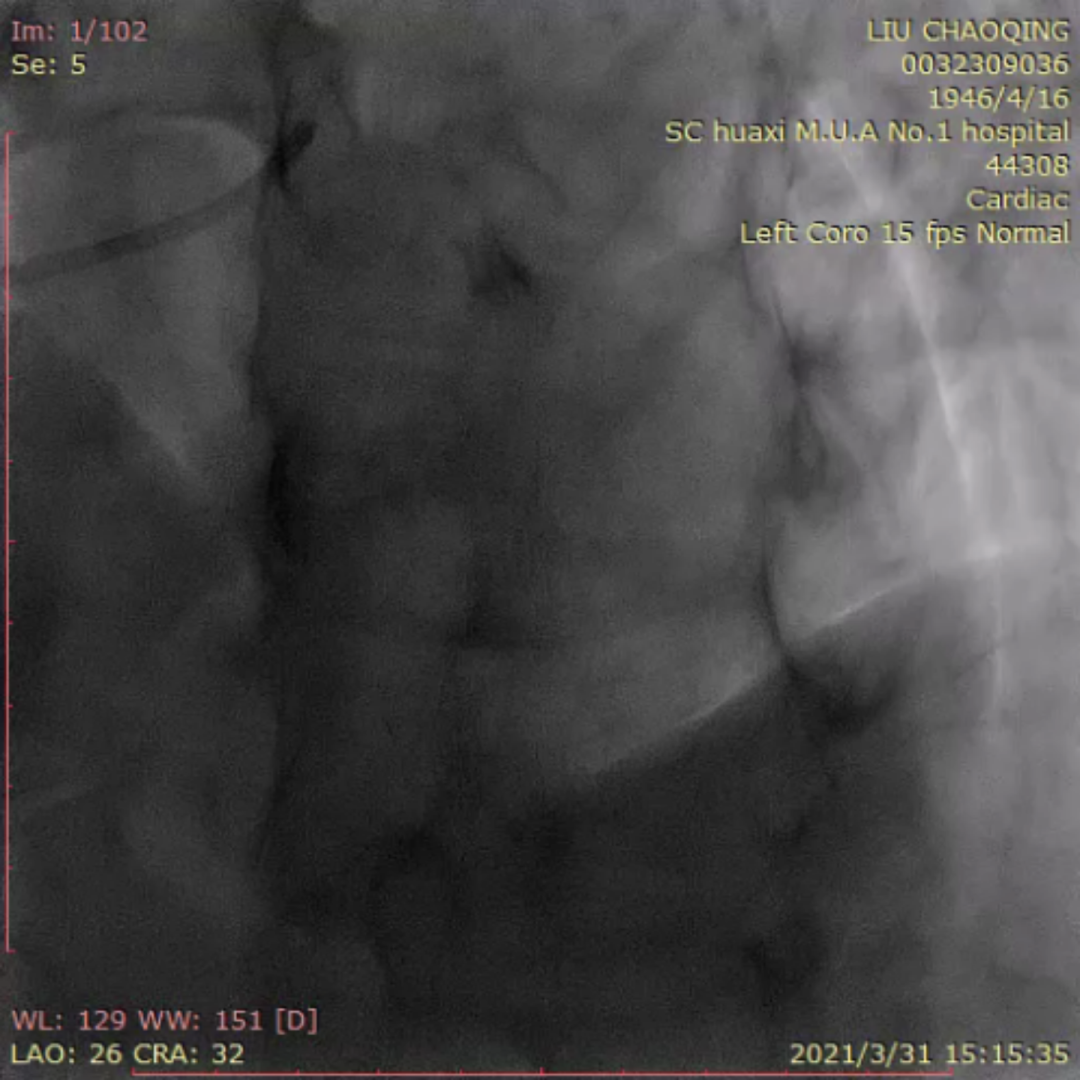

来自四川大学华西医院的李晨教授为大家分享了一例ADR开通前降支CTO的疑难病例。患者为老年男性,反复活动后胸痛6月。当地医院冠脉造影提示前降支完全闭塞,尝试PCI未能成功开通血管。予规范药物治疗,患者仍反复有胸痛入院。患者两段CTO,闭塞段长,钙化重,成角,前次失败,J-CTO 4分,右窦上方侧枝供应间隔-前降支;回旋支自身侧枝供应对角支;右冠无明显侧枝;前降支中段着陆区条件较好,ADR着陆区条件尚可。

右冠远端重度狭窄

右冠窦上方侧枝供应前降支

右窦造影显示侧枝较扭曲

双侧造影:右冠侧枝条件差,自身侧枝供应对角支

患者术中遭遇前降支导丝受阻,对侧和同侧造影前降支远端显影不清的问题。后双侧造影时可见对角支和前降支主支相通。同侧逆向可清晰显示对角支,若进入对角支真腔,可调整方向或通过KDL将导丝放入前降支。随后Pilot 200顺利进入对角支,导丝进入对角支分支。然而随后导丝在第二段闭塞重度钙化处进入假腔,从假腔进入对角支,在远端重回真腔。后启动ADR。最后李晨教授结合病例对逆向及ADR启动时机和ADR穿刺位点选择进行了发表了个人见解。